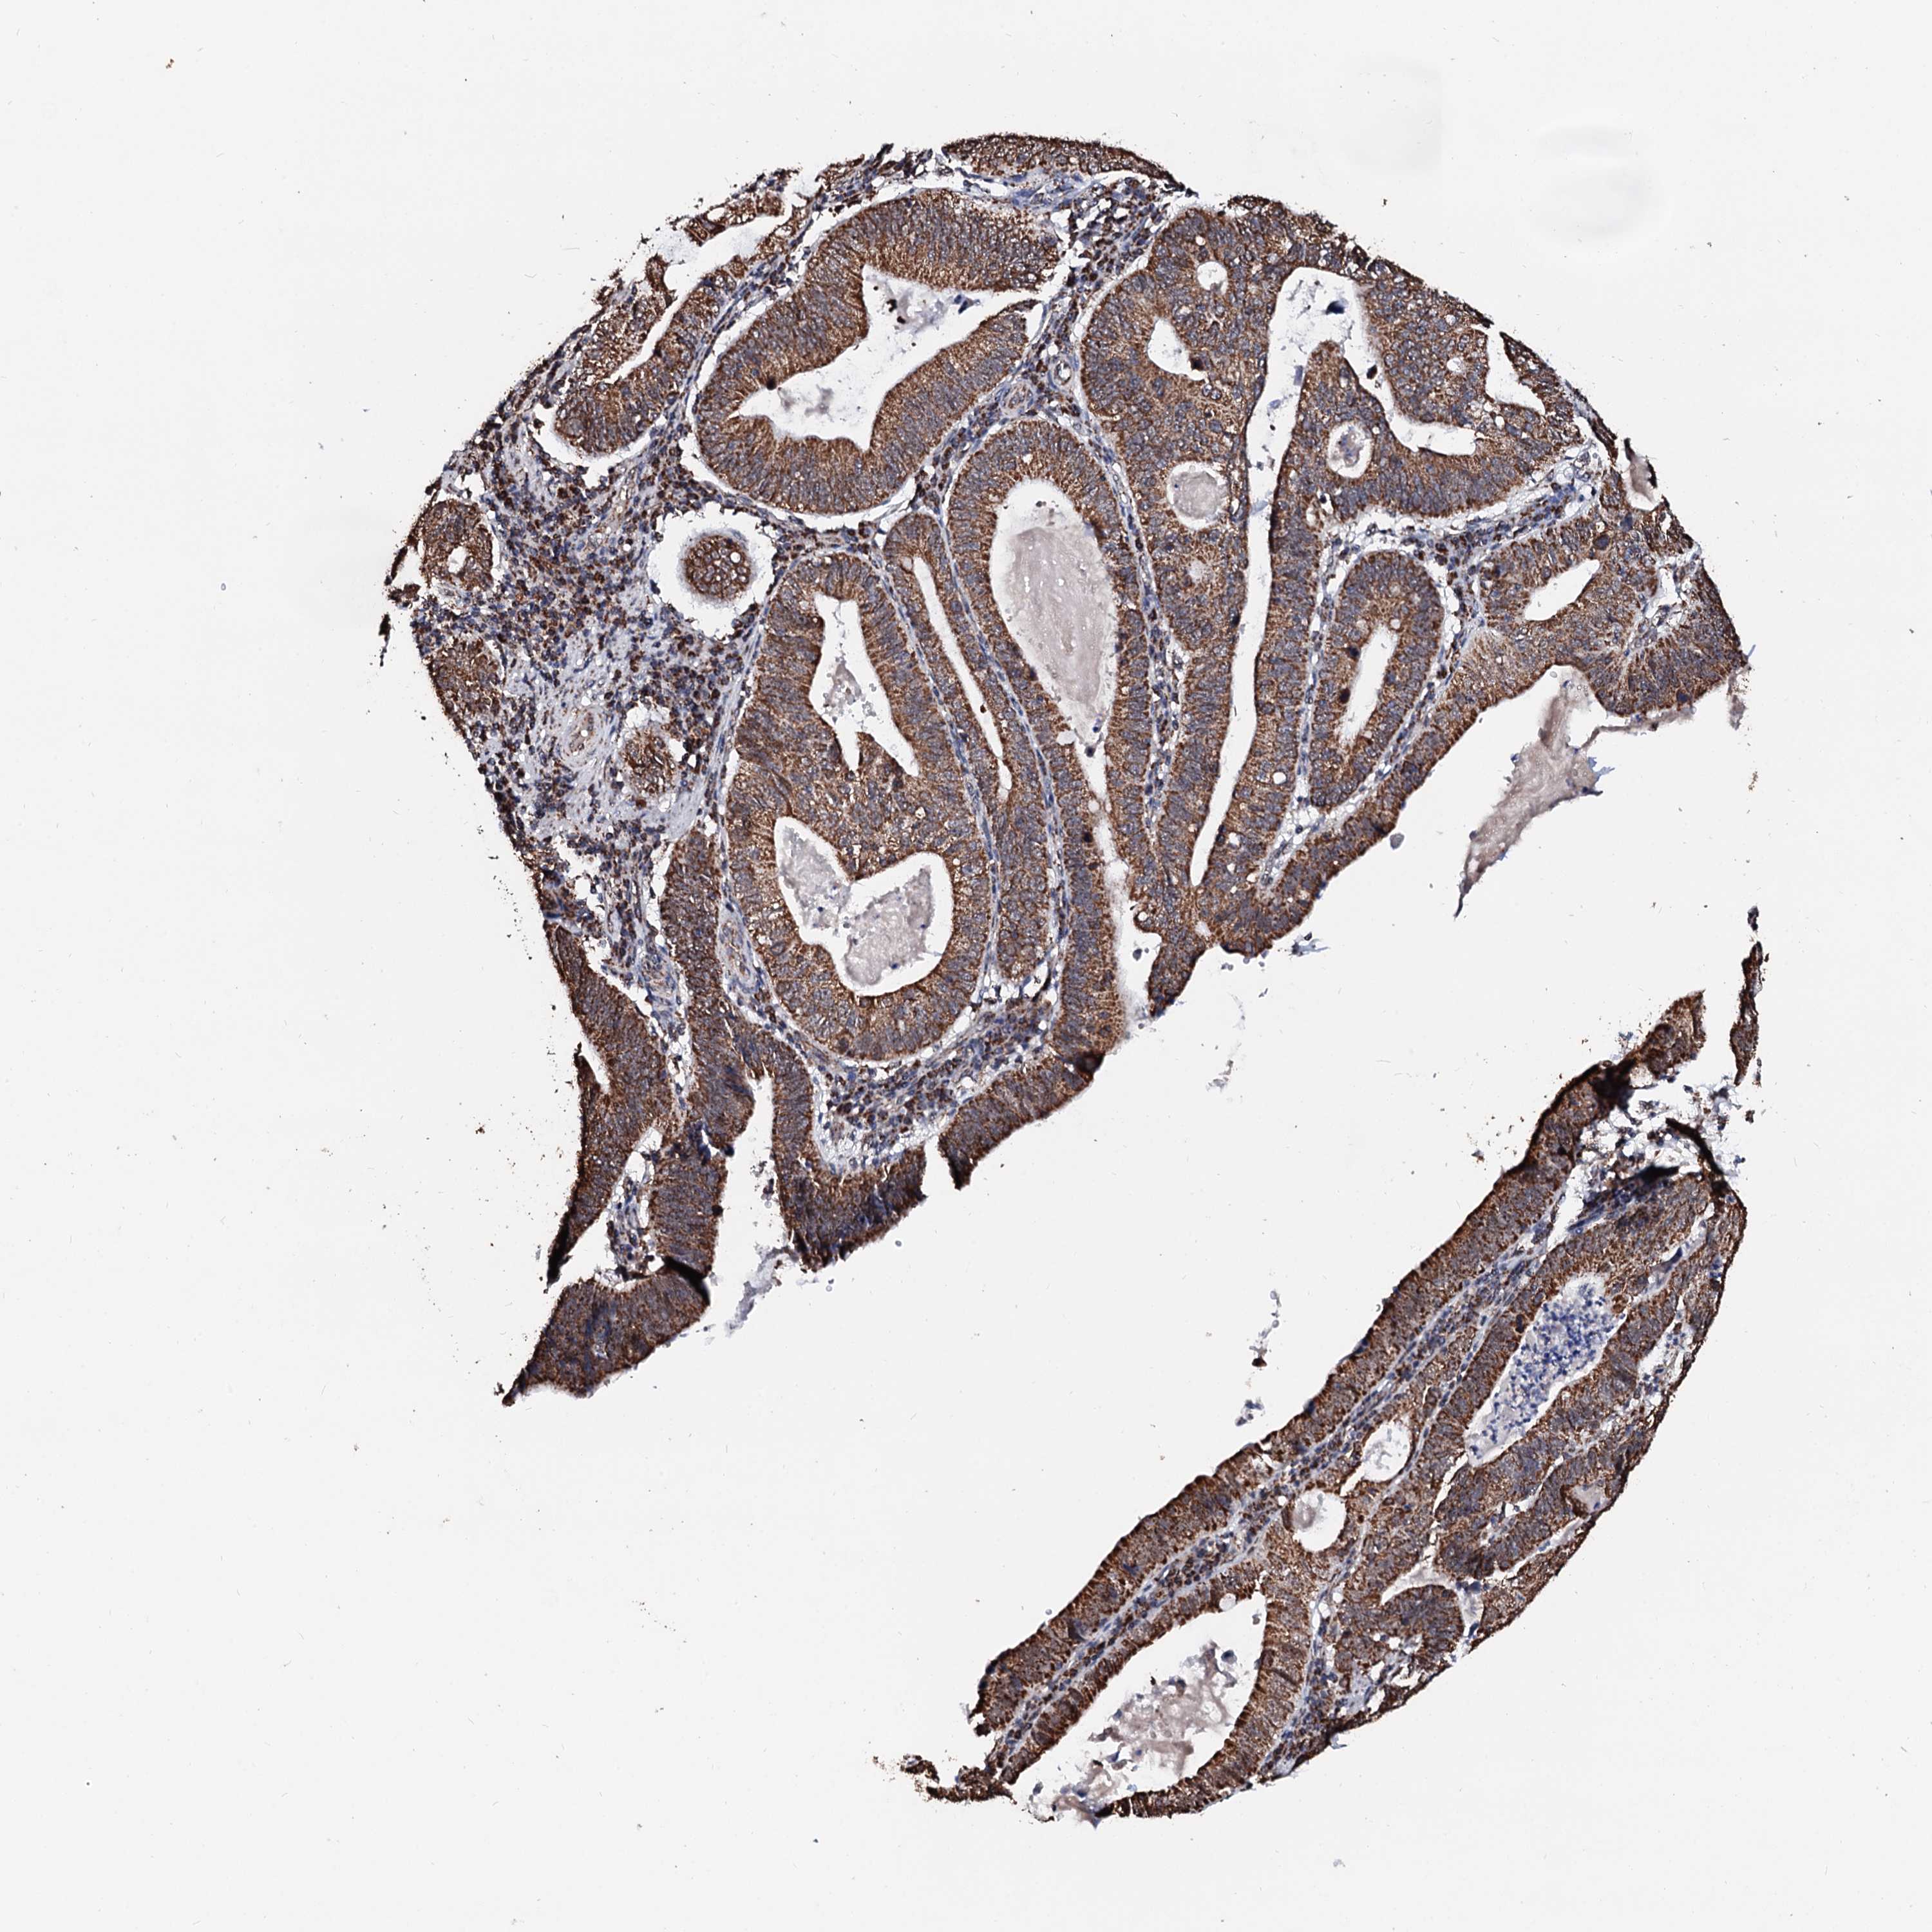

STOMACH CANCER - Protein expressioni

A mouse-over function shows sample information and annotation data. Click on an image to view it in a full screen mode. Samples can be filtered based on level of antibody staining by selecting one or several of the following categories: high, medium, low and not detected. The assay and annotation is described here.

Note that samples used for immunohistochemistry by the Human Protein Atlas do not correspond to samples in the TCGA dataset.

Antibody stainingi

Antibody staining in the annotated cell types in the current human tissue is reported as not detected, low, medium, or high, based on conventional immunohistochemistry profiling in selected tissues. This score is based on the combination of the staining intensity and fraction of stained cells.

Each image is clickable and will lead to virtual microscopy that enables deeper exploration of all samples and also displays staining intensity scores, fraction scores and subcellular localization as well as patient and tissue information for each sample.

Antibody HPA039875

Staining

High

Medium

Low

Not detected

Intensity

Strong

Moderate

Weak

Negative

Quantity

>75%

75%-25%

<25%

None

Location

Nuclear

Cytoplasmic/membranous

Cytoplasmic/membranous,nuclear

Adenocarcinoma, NOS